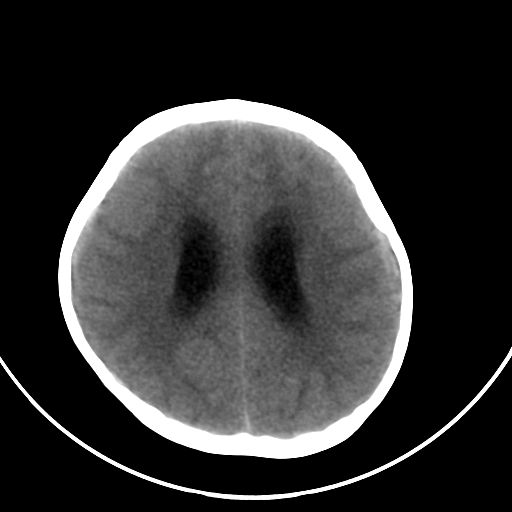

以下是引用zjzjr在2008-7-27 9:56:00的发言:[br]考虑髓母细胞瘤伴梗阻性脑积水.建议增强或mri

以下是引用子十在2008-7-27 9:53:00的发言:[br]考虑髓母细胞瘤